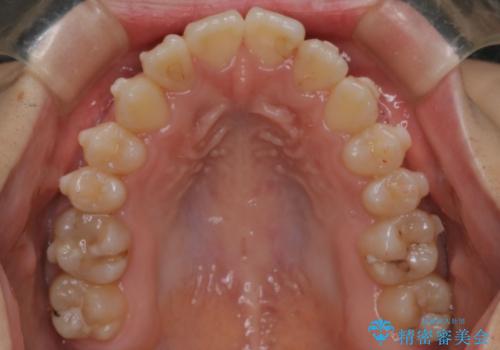

マウスピース矯正で前歯のガタツキを改善! 短期間で治療完了

- 前歯のガタツキが気になるとのことで来院されました。

前歯のガタツキに加え、奥歯の噛み合わせにも問題があったため、マウスピース矯正で治療し改善しました。